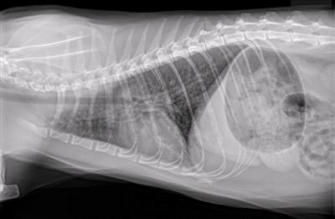

Lungs of a kitty with asthma